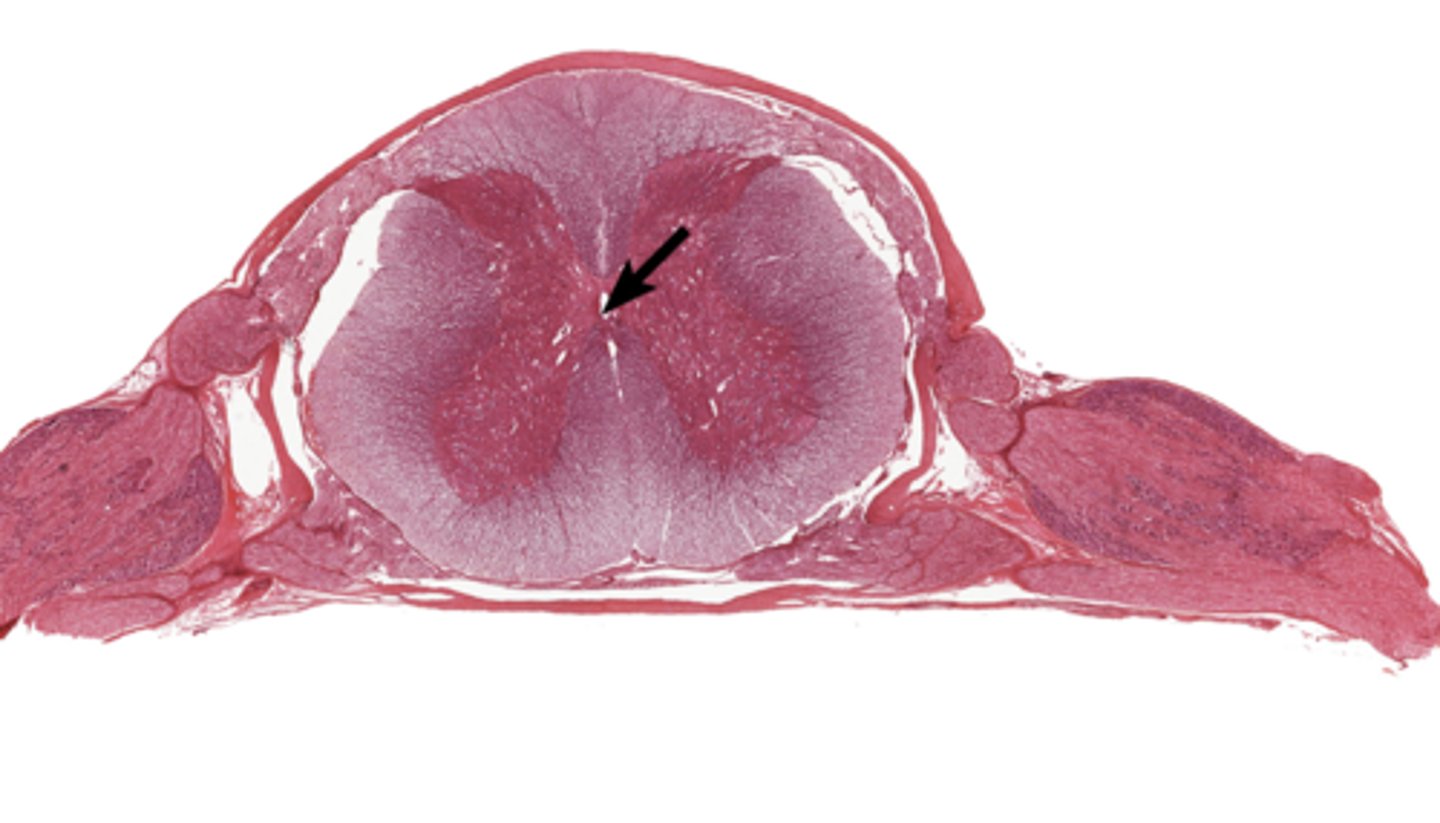

Dura mater

blue

Arachnoid mater

red

Pia mater

green

Epidural space

purple

Subdural space

between red and blue

Subarachnoid space

between red and green

Posterior root

purple

Posterior root ganglion

green

Posterior ramus

orange

Anterior root

blue

Anterior ramus

red